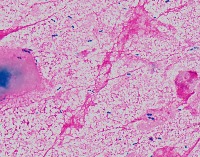

Medical Research: This model can be utilized in the field of medical microbiology and research to classify bacterial strains based on their visual characteristics in lab experiments and for the study of bacterial growth processes.

Healthcare Diagnostics: In healthcare, the "assembly" model could be used to assist in bacterial diagnosis in clinical lab settings, identifying the presence of specific forms of bacteria like Staphylococcus, Streptococcus, B-catarrhalis, Str_pne, and Enterococcus in samples.

Pharmaceutical Industry: The model could be applied in the development stages of antibiotics or bacterial treatments, helping to identify and study the response of specific bacterial strains to new drugs.